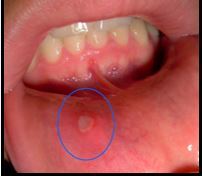

Diagnosis

A

Aphthous ulcers